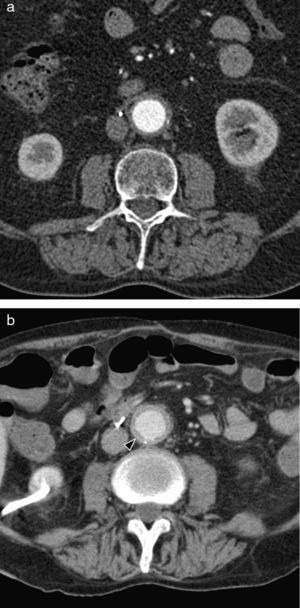

CT with intravenous contrast, in the initial stages of the disease, shows concentric wall thickening, which has been described as «double ring»2 (edematous and hypodense intima in the inside with the medium and the adventitia inflamed around, hypercaptant); in advanced or tardive stages stenosis, thrombosis and occlusions may be observed (Fig. 3a). Other findings associated are extensive mural calcifications, aneurysms and ulcers (Fig. 4a–c).

Takayasu's Arteritis of a 41-year-old woman with intestinal angor and right leg claudication. (a) CT study with contrast. Irregular-looking thoracoabdominal aorta with wall thickening (arrow heads). (b) MIP image of angio-MR showing stenosis in the ostium of both renal arteries (arrow heads) and in the primitive iliac arteries. (c) Angiographic correlation of the MR image findings. (d) Selective arteriography of the celiac trunk showing critical stenosis (arrow head) of 90% in the proximal portion thereof without distal affectation. (e) Successful implantation of Herculink low-profile expansible balloon endoprosthesis (arrow head) (of 7×18mm).

Takayasu's arteritis of a 34-year-old woman. (a) Axial CT image with contrast showing dilation and significant calcification of the ascending and descending thoracic aorta (arrow heads). (b) Axial CT cut with contrast. Abdominal aorta and upper mesenteric ostial artery wall thickening (arrow head). (c) MPR sagittal reconstruction. Parietal irregularity (arrow heads) and extensive calcification of the aorta. (d) Coronal MIP reconstruction of angio-MR of supraaortic trunks. Complete occlusion of both subclavian arteries in their prevertebral portions (black arrow heads) with posterior recannulation on the left side by cervical arteries (white arrow heads) and on the right side by the vertebral artery (arrow).